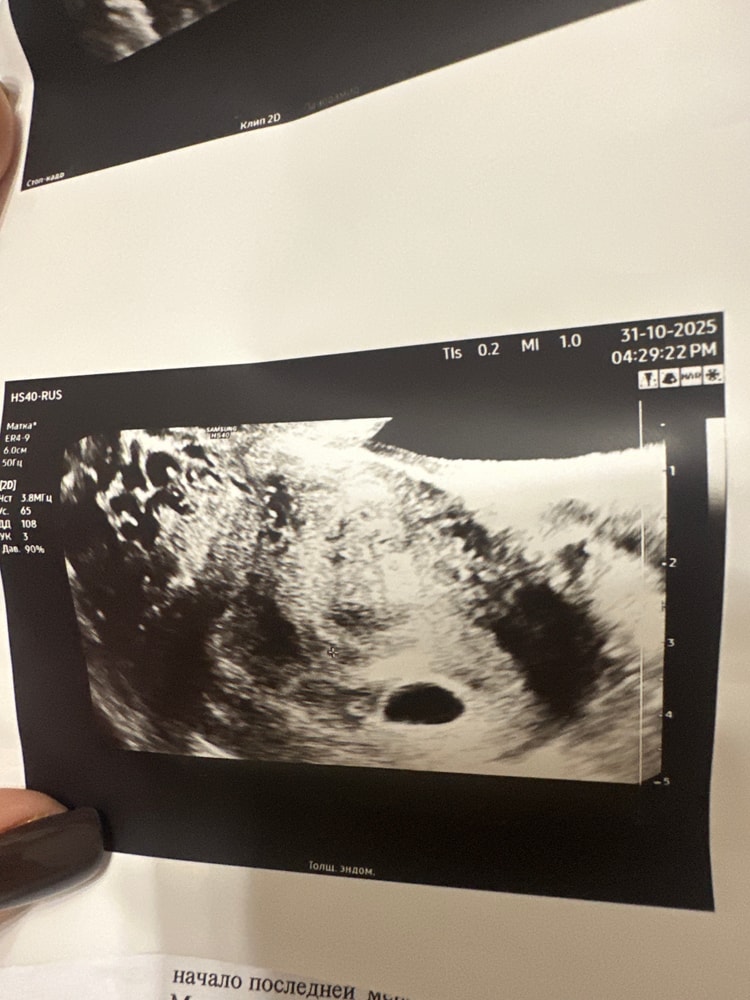

Если 24 числа было три недели, то сейчас только 4. Что они хотят там увидеть? У меня в 5 нед и три дня только появился желточный мешочек, эмбриона ещё не видели даже. Не думайте о плохом и сдайте хгч

Даже если у вас анэмбриония, ее ставят в 7-8 недель и выше, если нет ничего вообще в пя

Вам нужно сдать хгч в динамике и от этого уже плясать. В 4 недели у меня подтвердили маточную б и нашли пя и жм. А после я начала ходить на узи каждую неделю и смотреть, как растёт и развивается. Хгч был 1058.99 на следующий день я пошла на узи, но хгч ещё два раза сдавала для своего успокоения. Сердцебиение услышала на 7 нед ровно, пульсацию на 6нед3дня. Ищите хорошего узиста.

Сдать хгч 3 раза, каждые два дня, прибавка должна быть от 1,5 до 3 за 48 часов. На узи, когда хгч больше 1000 (одна тысяча), раньше ничего не увидите. Плюс выберете узиста эксперта в каком ниб перинатальном центре. Если узи аппарат слабый, все плохо видно. Пока у вас не информативно все, сейчас только ждать)))